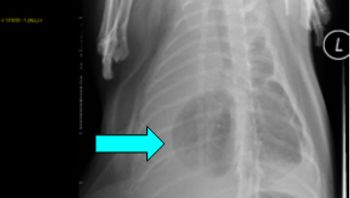

Pneumothorax is defined as free air in the pleural space. Normal intra-pleural pressure is about - 5 cmH20, which means that in order to equilibrate pressures, air from either the atmosphere, or the lung will equilibrate rapidly with the pleural space. Pneumothorax can be further characterized as traumatic, spontaneous and iatrogenic.

The pleural space is defined as the area between the lungs and the chest wall. Normally there is no soft tissue or free air present in this space. A very small amount of fluid (undetectable on radiographs or ultrasound) may be present within the thoracic cavity. Clinical signs of pleural space disease include tachypnea or difficulty breathing.